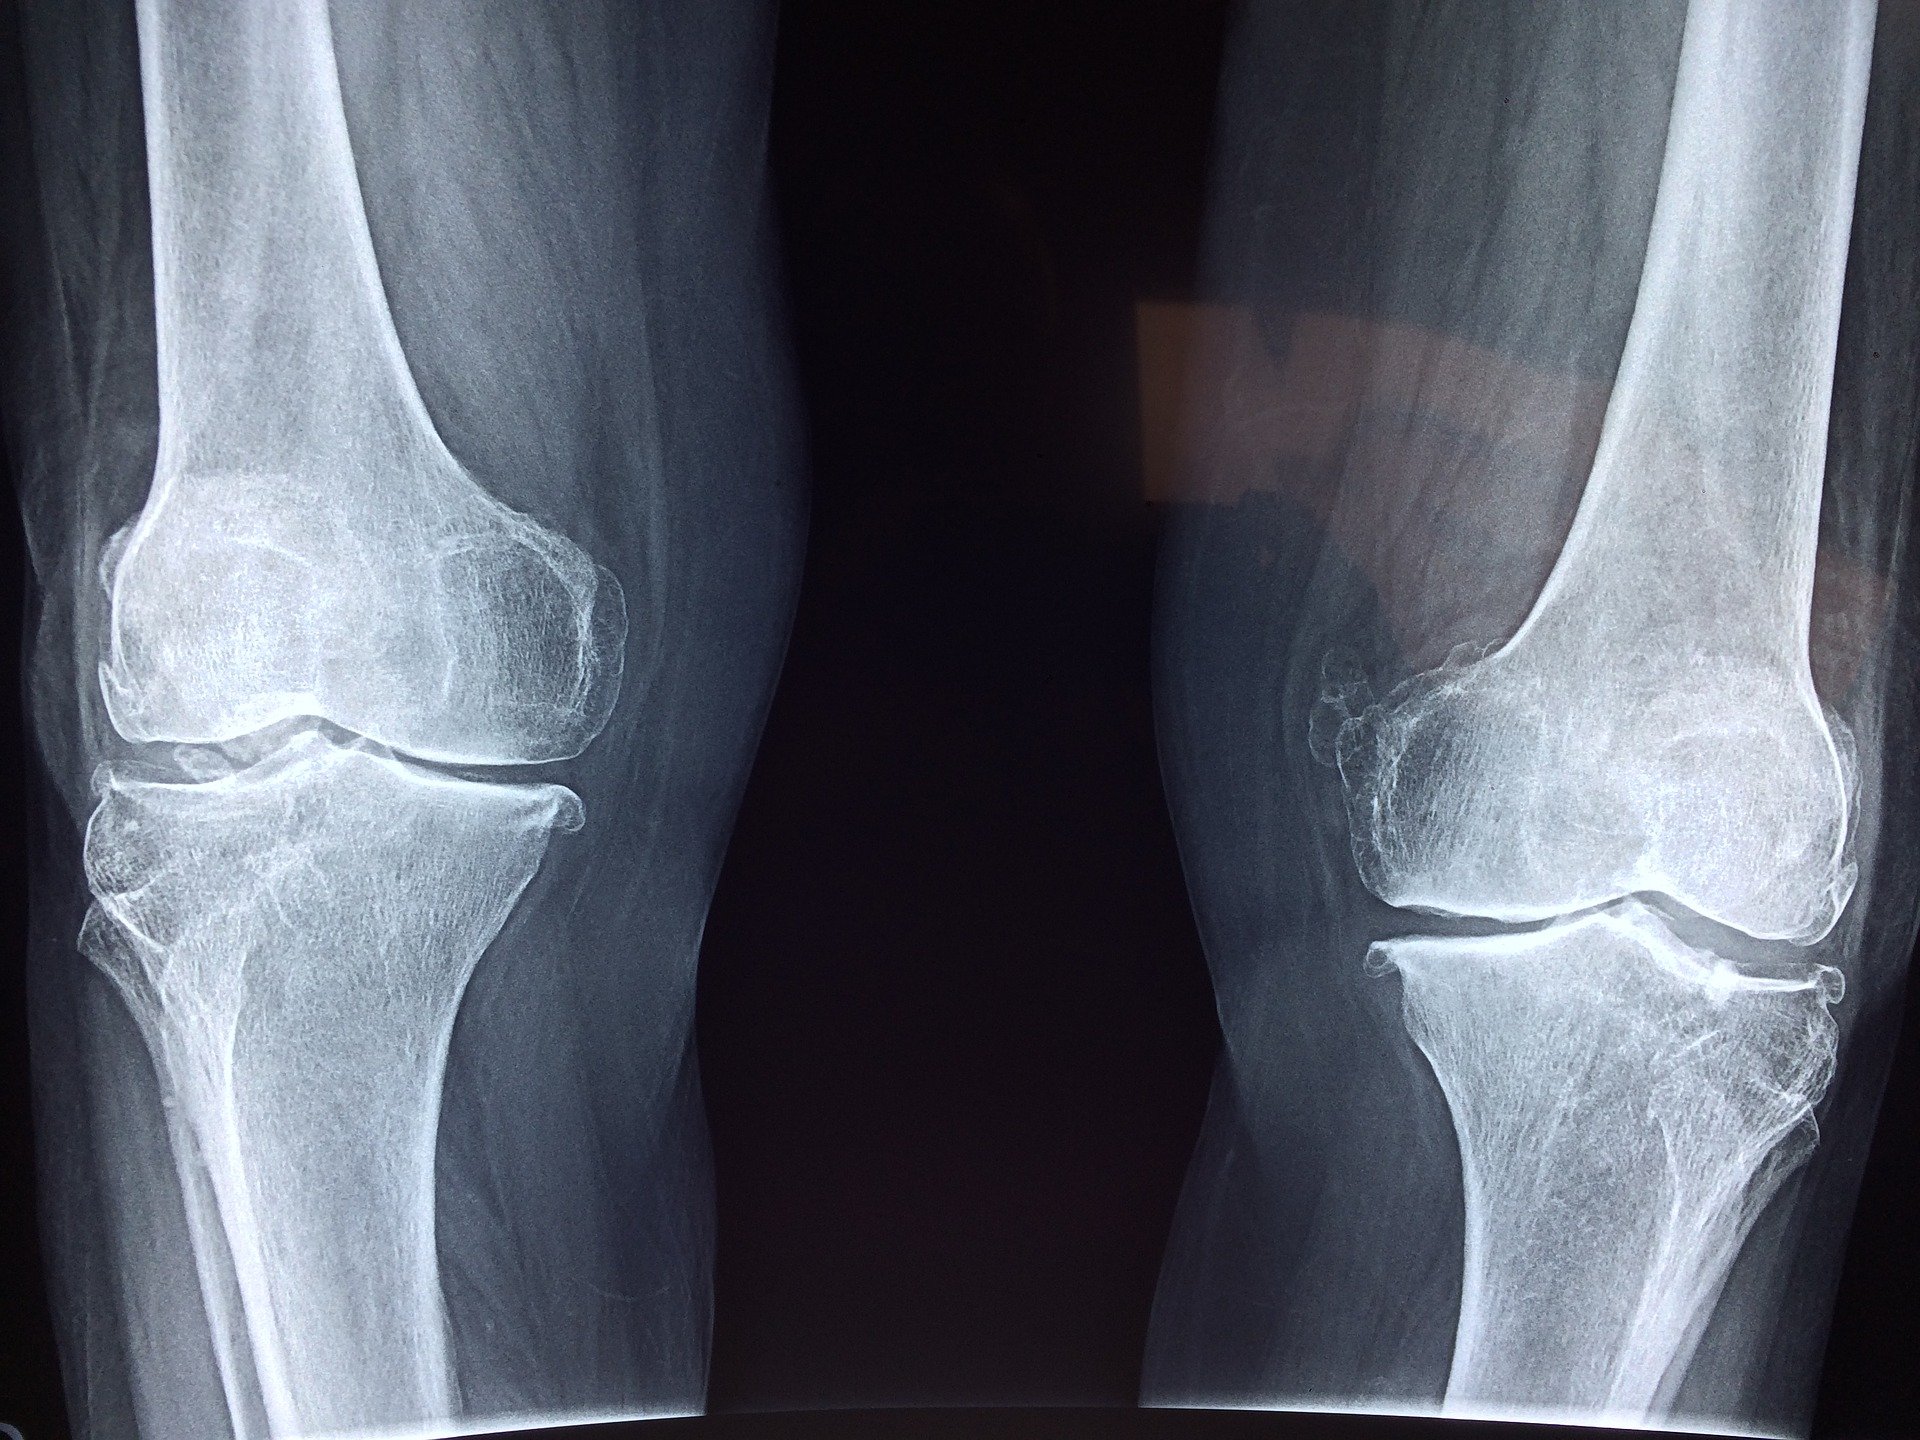

กระดูกอ่อนที่อยู่ติดกันอาจไม่ได้รับการหล่อลื่นที่เพียงพอจากของเหลวไขข้อและกันกระแทกจากกระดูกอ่อน เมื่อพื้นผิวของกระดูกสัมผัสกันโดยตรงมันจะส่งผลให้เกิดความเจ็บปวดและการอักเสบของเนื้อเยื่อรอบ ๆ

เมื่อกระดูกแตกกันอย่างต่อเนื่องพวกมันจะหนาขึ้นและเริ่มมีการสร้าง osteophytes หรือกระดูกสเปอร์